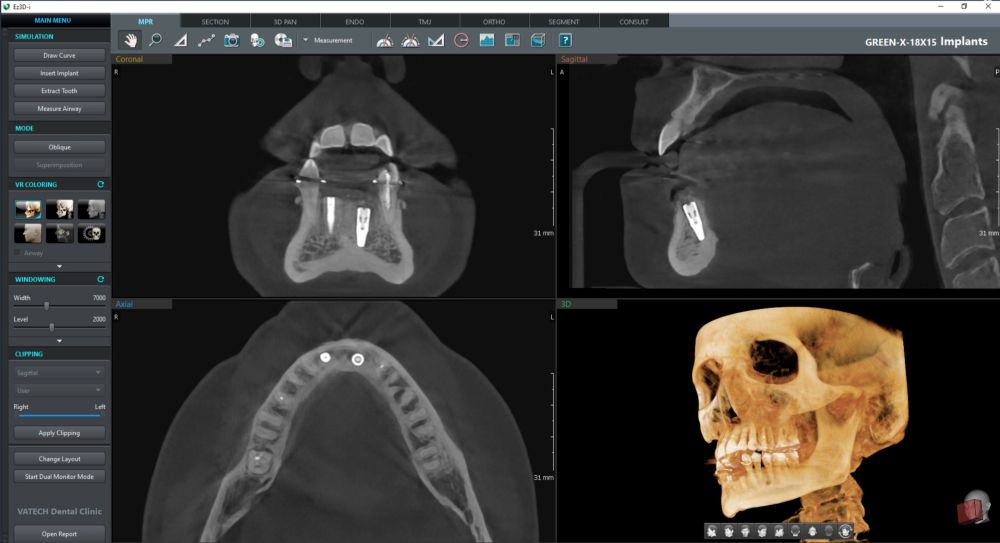

W naszej pracowni korzystamy z najnowszego tomografu Vatech Green X (2025). To aparat, który daje bardzo dokładny obraz, a jednocześnie wykorzystuje niską dawkę promieniowania — dlatego jest bezpieczny także dla dzieci i osób, które muszą wykonywać badania częściej.

- wyraźne obrazy 2D i 3D — pomocne przy implantach, ósemkach, leczeniu kanałowym i ortodoncji

- szybkie skanowanie CBCT — już od 2,9 sekundy

Tomografia CBCT tworzy trójwymiarowy obraz zębów, kości, zatok i stawów.

Pozwala na precyzyjne planowanie:

- implantów,

- usuwania ósemek,

- leczenia kanałowego,

- aparatów ortodontycznych,

- diagnostyki bólu zatok i stawu skroniowo-żuchwowego.

Badanie jest szybkie, bezbolesne i nie wymaga żadnego przygotowania.